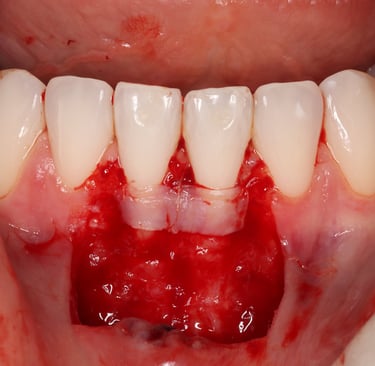

Chirurgie muco-gingivale

Traitement des récessions gingivales